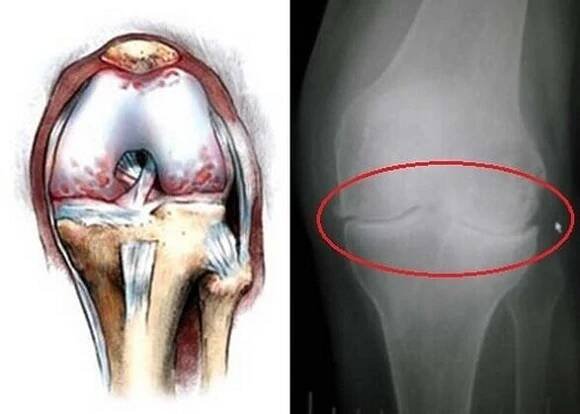

Gonartróza 3. stupně

Gonartróza 2 stupně kolene | Jan Anděl

Gonartróza stupně kolenního kloubu, typy, metody léčby / Gonartróza